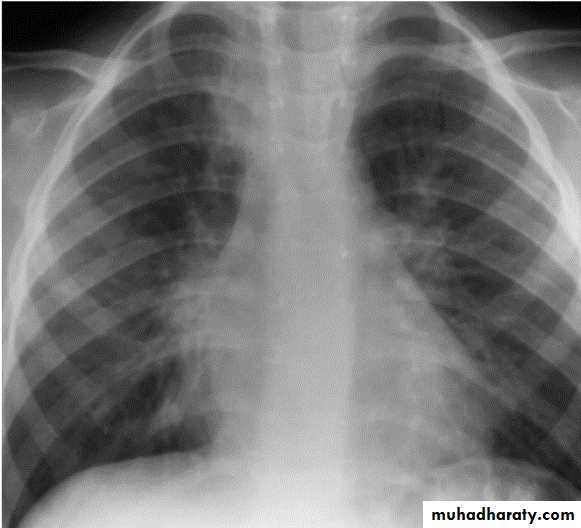

Bronchopneumonia

Viral pneumonia characteristically shows diffuse, streaky infiltrates of bronchopneumonia.